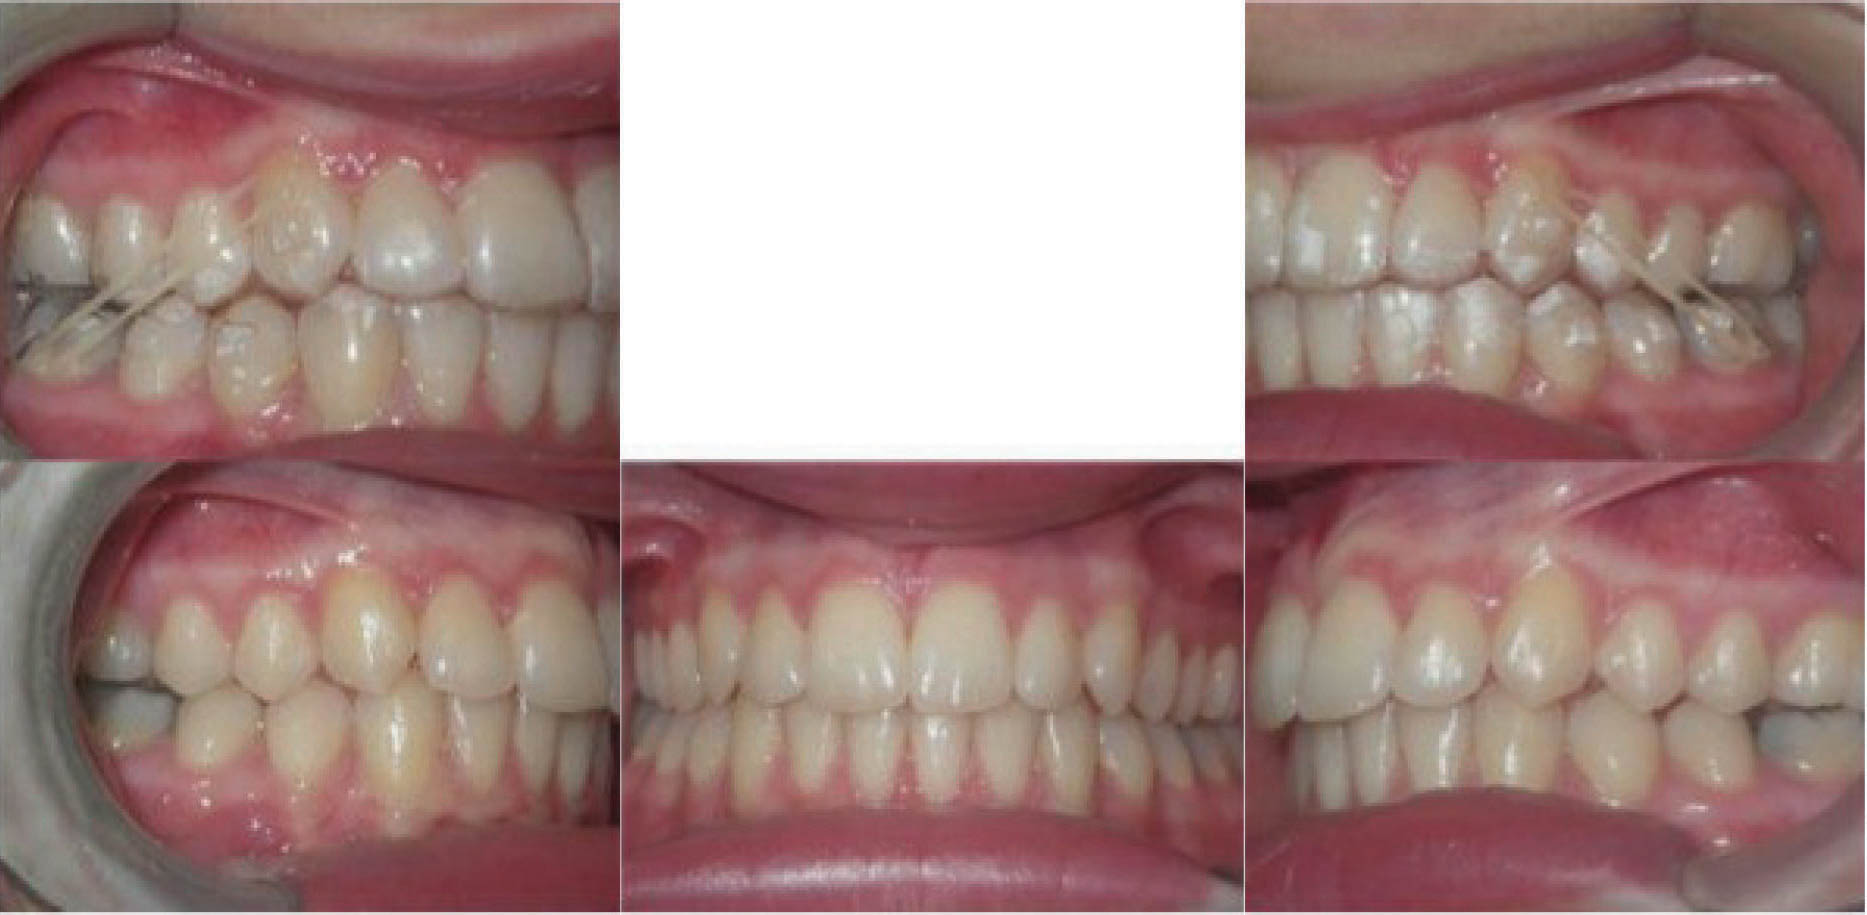

بیمار بعدی یک دختر ۱۶ ساله ClII/1 با اوربایت نرمال و اورجت زیاد است. کرادینگ مختصر دو فک دارد، قوس بالا تنگ، و پروفایل او طبیعی است (شکل 83-۶ الی 85-۶). در این بیمار از الاستیک کلاسII استفاده شده است. الگو اسکلتی طبیعی، رادیوگرافی لترال سفالومتری نشان دهنده دندانهای قدامی پروترود شده بالا با الگو طبیعی اسکلتی میباشد. رادیوگرافی OPG طبیعی است. قسمت بعُد افقی چک لیست را به این نحوه پر کردیم:

از الاستیک کلاسII برای اصلاح رابطه افقی استفاده گردیده است. شروع الاستیک کلاسII بعد از مرتب شدن دندانها بود و از الاستیک ۴ انسی استفاده نمودیم چون میزان اصلاح زیاد بود.

در انتهای درمان (شکلهای 89-۶ الی 91-۶) اکلوژن کلاسI شده است. دندانها مرتب شدند و اوربایت و اورجت طبیعی و به حداکثر زیبایی دست یافتیم. عکس نهایی OPG طبیعی است. مقایسه عکسهای لترال ابتدا و انتهای درمان نشاندهنده تغییر قابل ملاحظه موقعیت انسیزورهای بالا است که منجر به اصلاح اورجت گردیده است. لبخند او عالی گردید.

نتیجه: کل درمان ۲۲ ماه به طول انجامید، 45 الاینر و الاستیک کلاسII ۴ انسی.